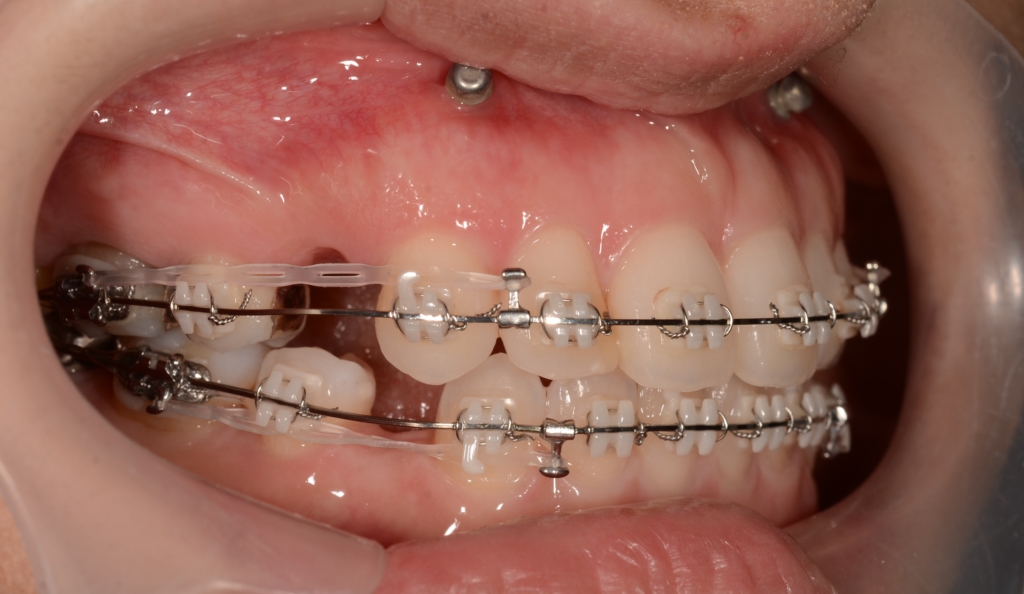

マルチブラケットシステム(スタンダードtype)で矯正を開始。

上の歯列がきれいに並んで、アンカースクリューを植立する目途がついたので、上顎の口蓋正中部、臼歯部と前歯部の頬側辺りにアンカースクリューを植立しました。(計6本)

奥歯の圧下による下顎の反時計回りの回転を狙っています

前歯部の噛み合わせに目途が付いた時点で、下の歯にも装置を付けて、合わせて治療を進めます。

噛み合わせがしっかりしたところで、上下とも第一小臼歯を抜歯して前歯を後方へ最大限に引っ込めて行きます。